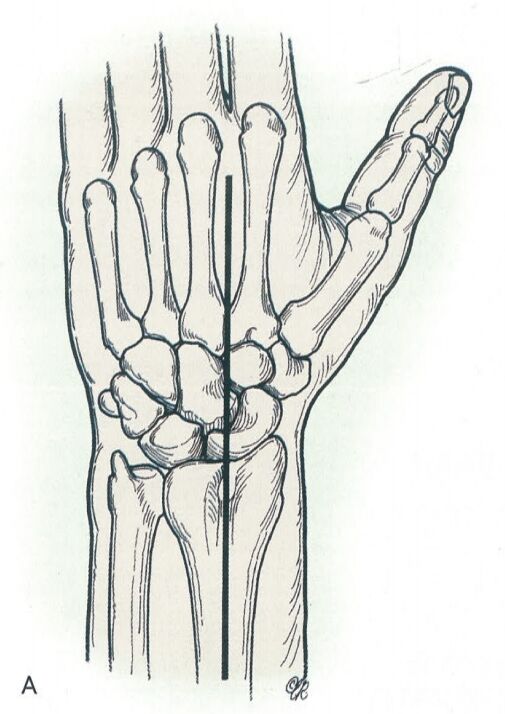

桡腕关节融合切口:沿第三掌骨和腕掌关节中点处做长约8cm纵行切口